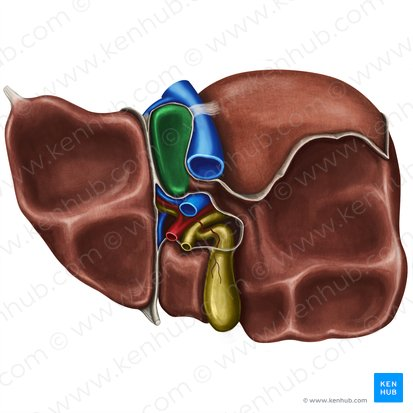

Quadrate Lobe

A small, quadrilateral lobe of the liver located inferiorly and medially on the visceral surface, bordered by the gallbladder and the fissure for the round ligament.

Caudate Lobe

A small lobe of the liver located posteriorly on the visceral surface, near the inferior vena cava and the fissure for the ligamentum venosum.

Gallbladder

A small, pear-shaped organ located beneath the liver that stores and concentrates bile produced by the liver.

Right Hepatic Duct

A duct that carries bile produced by the right lobe of the liver.

Left Hepatic Duct

A duct that carries bile produced by the left lobe of the liver.

Common Hepatic Duct

The duct formed by the union of the right and left hepatic ducts, which carries bile away from the liver.

Cystic Duct

The duct that connects the gallbladder to the common hepatic duct, allowing bile to enter and exit the gallbladder.

Hepatic Artery

A branch of the celiac artery that supplies oxygenated blood to the liver.

Hepatic Portal Vein

A large vein that carries deoxygenated but nutrient-rich blood from the digestive organs (stomach, intestines, spleen, pancreas) to the liver for processing.

Inferior Vena Cava

A large vein that carries deoxygenated blood from the lower and middle body back to the heart.